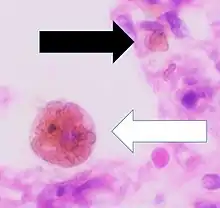

A siderophage is a hemosiderin-containing macrophage. Heart failure cells are siderophages generated in the alveoli of the lungs of people with left heart failure or chronic pulmonary edema, when the high pulmonary blood pressure causes red blood cells to pass through the vascular wall.[1] Siderophages are not specific of heart failure. They are present wherever red blood cells encounter macrophages, such as pulmonary hemorrhage.

In left heart failure, the left ventricle can not keep pace with the incoming blood from the pulmonary veins. The resulting backup causes increased pressure on the alveolar capillaries, and red blood cells leak out. Alveolar macrophages (dust cells) engulf the red blood cells, and become engorged with brownish hemosiderin.